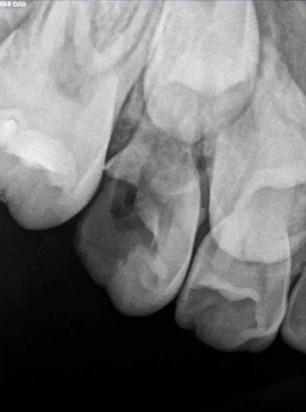

37继发龋!根尖炎?

曲面断层片怎么看口腔精读 | 一次性教你看懂曲面断层片!_https://www.jmylbn.com_新闻资讯_第56张

曲面断层片怎么看口腔精读 | 一次性教你看懂曲面断层片!_https://www.jmylbn.com_新闻资讯_第57张

25远中邻面浅龋

曲面断层片怎么看口腔精读 | 一次性教你看懂曲面断层片!_https://www.jmylbn.com_新闻资讯_第58张

曲面断层片怎么看口腔精读 | 一次性教你看懂曲面断层片!_https://www.jmylbn.com_新闻资讯_第59张